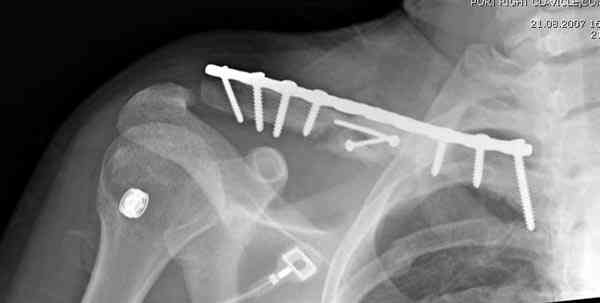

Второй случай тоже недавно оперирован по поводу

ложного сустава, в марте травма, через 4.5 половиной

операция..

Описанный случай это больная моего партнера, мы недавно случай разбирали на нашей конференции (Morbidity and Mortality Conference аналог клинического разбора)

Выставлен как пример, к чему может привести

неудачно выбранный фиксатор.

Больные иногда пропадают из нашего поле зрения, ту больную неудачно оперировал в нашем городе специалист по спортивной медицине. Он же направил к нам после удаления фиксатора.